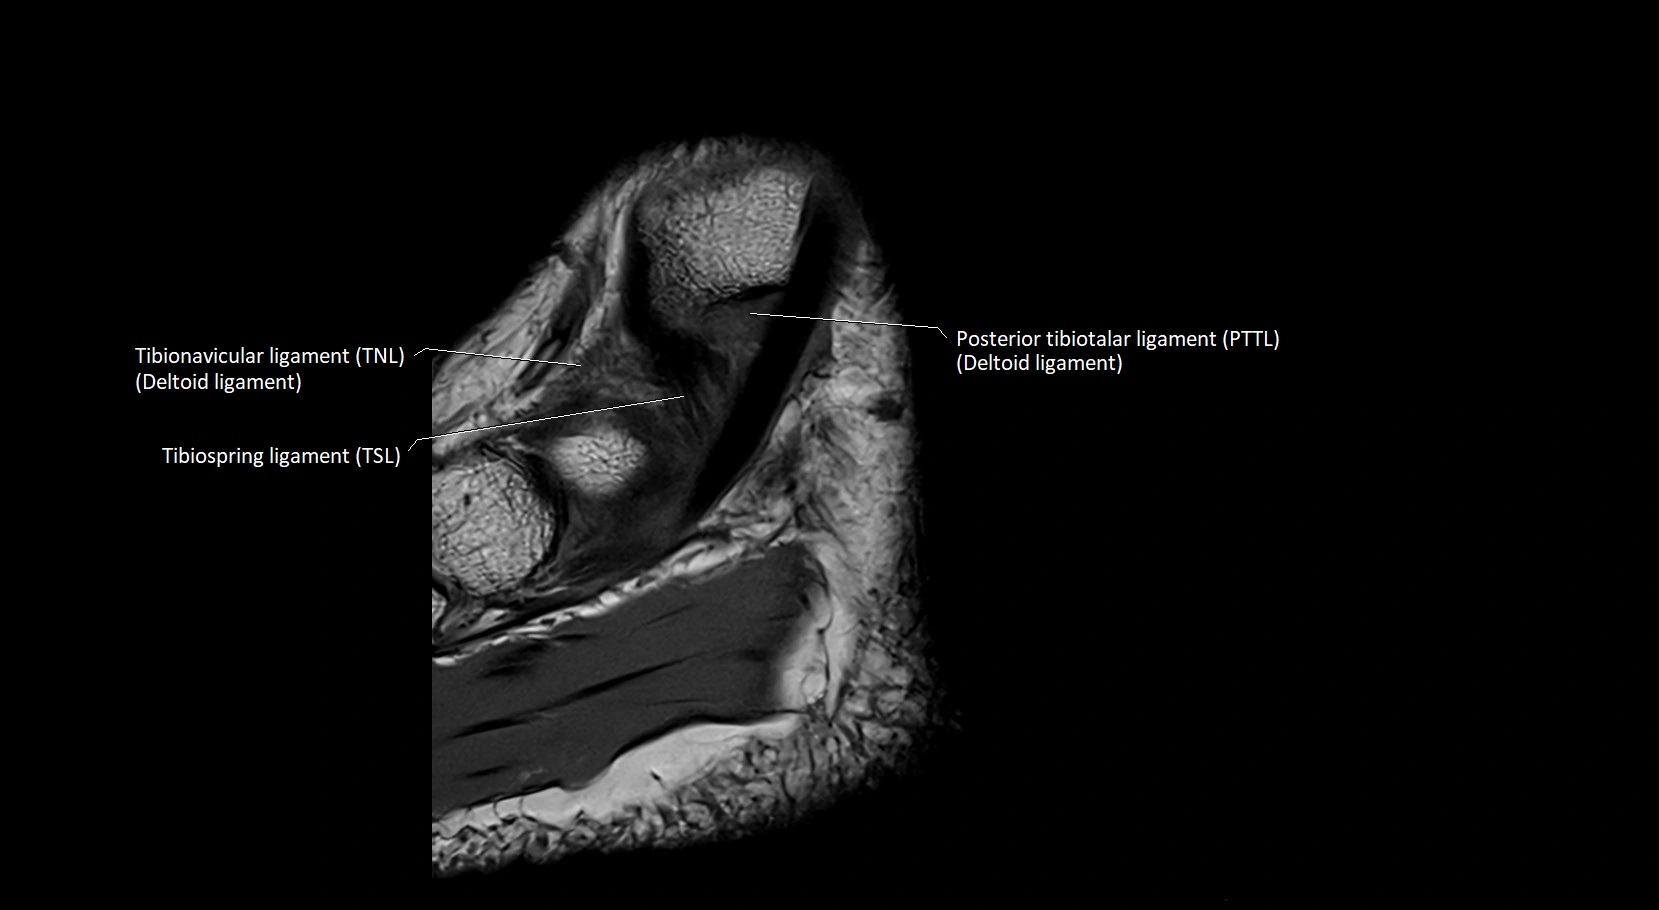

MRI image

image